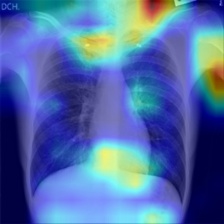

In order to compare the interpretability capacity of our model and the state-of-the-art models, we employ Grad-Cam [18] for heatmap visualizations on selected X-ray images. We show on a side-by-side basis how our model performs with superiority in Figures 4-7. We also observe that the addition of the attention block has a crucial role in focusing on the most relevant features in the images, which significantly assists the model during classification.